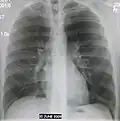

| A chest X-ray showing a very prominent wedge-shape bacterial pneumonia in the right lung | |

The discovery of x-rays made it possible to determine the anatomic type of pneumonia without direct examination of the lungs at autopsy and led to the development of a radiological classification. Early investigators distinguished between typical lobar pneumonia and atypical (e.g. Chlamydophila) or viral pneumonia using the location, distribution, and appearance of the opacities they saw on chest x-rays. Certain x-ray findings can be used to help predict the course of illness, although it is not possible to clearly determine the microbiologic cause of a pneumonia with x-rays alone.

Normal AP CXR

AP CXR showing left lower lobe pneumonia associated with a small left sided pleural effusion -

AP CXR showing right lower lobe pneumonia -

AP CXR showing pneumonia of the lingula of the left lung -

Right upper lobe pneumonia as marked by the circle. -

Left upper lobe pneumonia with a small pleural effusion.

Right lower lobe pneumonia as seen on a lateral CXR